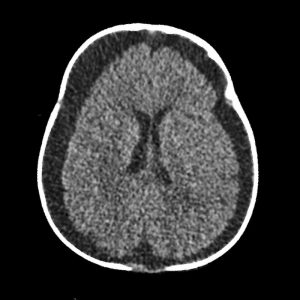

📣📣📣Haftanın ödüllü olgu sorusu yayınlandı.

Yanıtlarınızı www.tnrd.org.tr adresinden bekliyoruz.